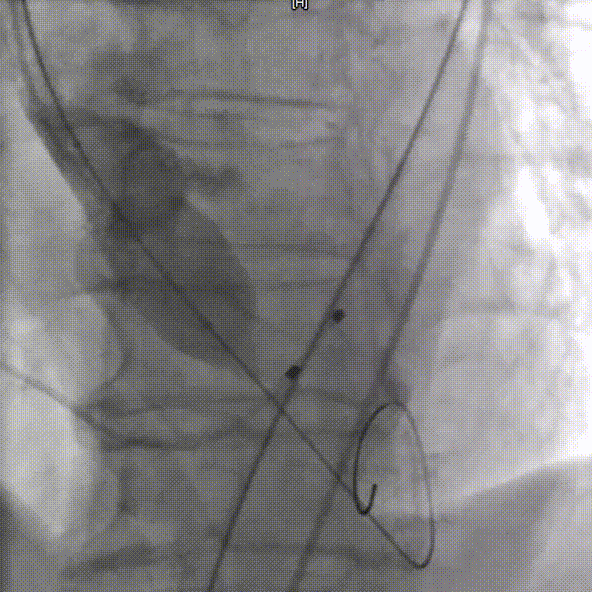

手术过程概览

右侧主入路造影

左侧辅入路造影

主动脉根部造影

18mm球囊预扩,冠脉灌注良好

输送器过弓

瓣下3mm定位

左冠窦侧偏深,需回收再定位

回收调整至零位定位,释放到工作位位置合适

完全释放后无反流,冠脉灌注良好

超声看位置合适,无反流

降主动脉良好

外周入路良好

患者压差从64mmHg降为4mmHg,效果显著。